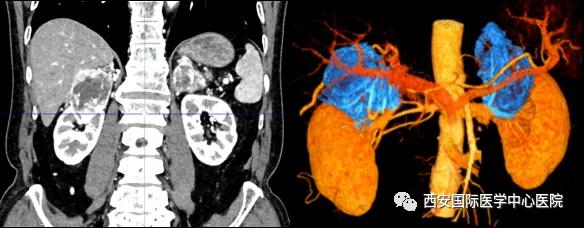

今年七十五歲的患者,來自陜西省商洛市,四月前因腰背部疼痛就診于當?shù)蒯t(yī)院,行CT檢查發(fā)現(xiàn)“右腎、雙側腎上腺占位,前縱膈淋巴結腫大,雙肺多發(fā)結節(jié)、胸椎骨質破壞,考慮轉移瘤”。為進一步診斷治療,患者的兒子帶他來到西安某三甲醫(yī)院,查泌尿系CT提示“右腎占位性病變,多考慮腎癌,雙側腎上腺多發(fā)轉移灶,腹膜后多發(fā)腫大淋巴結”;行穿刺活檢提示“腎透明細胞癌”;并給予患者口服靶向藥物的治療方案。

自四月份至今,患者一直口服靶向藥物治療(阿昔替尼5mg 2次/日),期間無不良反應,目前腰背部疼痛癥狀也有所緩解,復查影像學資料提示瘤體較前縮小,腫瘤完整切除的可能性明顯提高;而且患者的兒子也是一名外科醫(yī)生,所以他更想為父親完成后續(xù)的手術治療。

患者一家慕名前來到西安國際醫(yī)學中心醫(yī)院找到楊增悅教授。楊增悅教授仔細看完患者的之前的影像學及病理資料后,診斷為:右腎透明細胞癌(T4N1M1);并安排他住院。而后,主管醫(yī)生及時為他完善了術前檢查及評估。7月15日,在麻醉手術中心柴偉主任、王彬榮副主任、李娟護士長、李瑞剛護士長及全體麻醉手術中心團隊的有力保障下,成功完成了這臺“大”手術。

手術由楊增悅教授主持,舒濤主治醫(yī)師、王東主治醫(yī)師主刀,黃怡醫(yī)師、王平醫(yī)師協(xié)助完成。由于第四代達芬奇機器人更加靈活和精準的特性,手術全程順利,尤其是完全精準的“解鎖”了右腎動脈和右腎靜脈的數(shù)十根交互纏繞的分支血管。術后患者麻醉恢復后生命體征平穩(wěn),順利返回泌尿外科普通病區(qū)進一步康復。